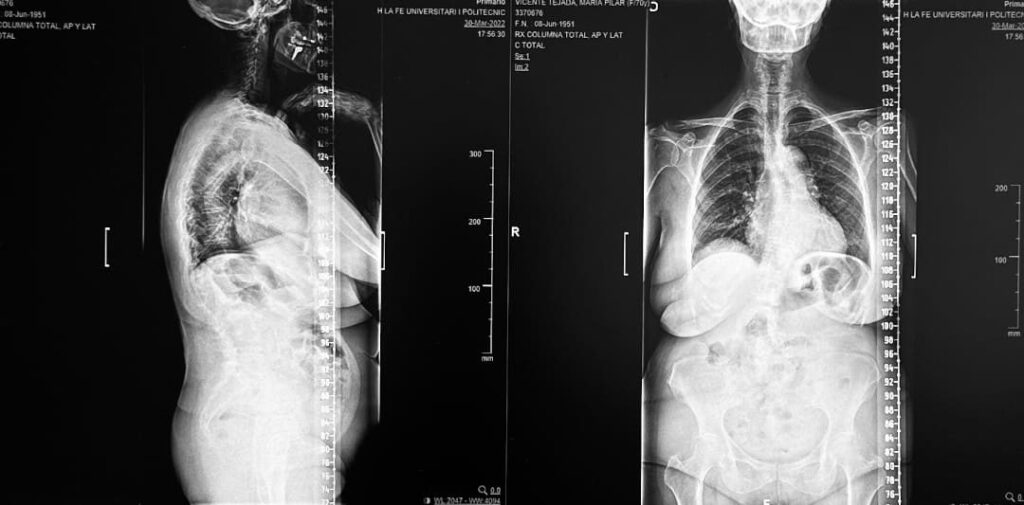

La escoliosis lumbar del adulto es una deformidad de la columna vertebral caracterizada por una desviación lateral en la región lumbar, que suele asociarse con desgaste degenerativo de los discos intervertebrales y las articulaciones facetarias. Este trastorno puede provocar dolor crónico en la zona baja de la espalda, alteraciones posturales, debilidad muscular y, en casos avanzados, compresión de raíces nerviosas, lo que genera síntomas como dolor irradiado a las piernas, debilidad o dificultad para caminar.

El Dr. Botella-Asunción, destacado neurocirujano en Valencia, es un referente en el uso de tecnología avanzada para la corrección quirúrgica de la escoliosis lumbar del adulto. La implementación de guías 3D personalizadas representa un avance significativo en este tipo de cirugías. Este enfoque combina imágenes de alta resolución con planificación preoperatoria detallada para diseñar guías específicas que se ajustan a la anatomía única del paciente.

El procedimiento comienza con un estudio exhaustivo de imágenes como radiografías, tomografía computarizada (TC) y resonancia magnética (RM). Con esta información, se diseña una guía tridimensional que facilita la colocación de tornillos pediculares y otros dispositivos de fijación. Durante la cirugía, el Dr. Botella-Asunción emplea estas guías junto con sistemas de navegación intraoperatoria para garantizar una corrección precisa de la escoliosis y la descompresión de las estructuras nerviosas afectadas.